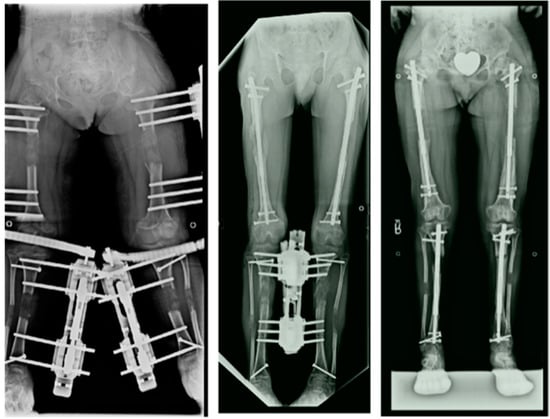

The usual goal in the tibias was 15–16 cm and the goal in the femurs was 10–12 cm. Since 1997, the author switched to simultaneous 4-segment lengthening of both femurs and both tibias at the same time using external fixation [5] (Figure 2, Figure 3, Figure 4, Figure 5, Figure 6 and Figure 7). The femurs were lengthened to a maximum goal of 8 cm and the tibias to 7 cm, for a total gain in height of 15 cm. This method was later modified to do bilateral femoral lengthening with implantable lengthening nails simultaneous with bilateral tibial lengthening with external fixation (Figure 8 left). This was referred to as 4-segment hybrid lengthening (Figure 8 middle). Since 2014, with the advent of shorter and smaller diameter implantable lengthening nails, 4-segment femur and tibia all implantable nail lengthenings were performed (Figure 8, right) [6,7].

Figure 8.

Radiographs showing 4-segment lengthening with: 4 external fixators (left); Hybrid, 2 implantable lengthening nails in both femurs and two external fixators (middle); and 4 implantable lengthening nails in both femurs and tibias.